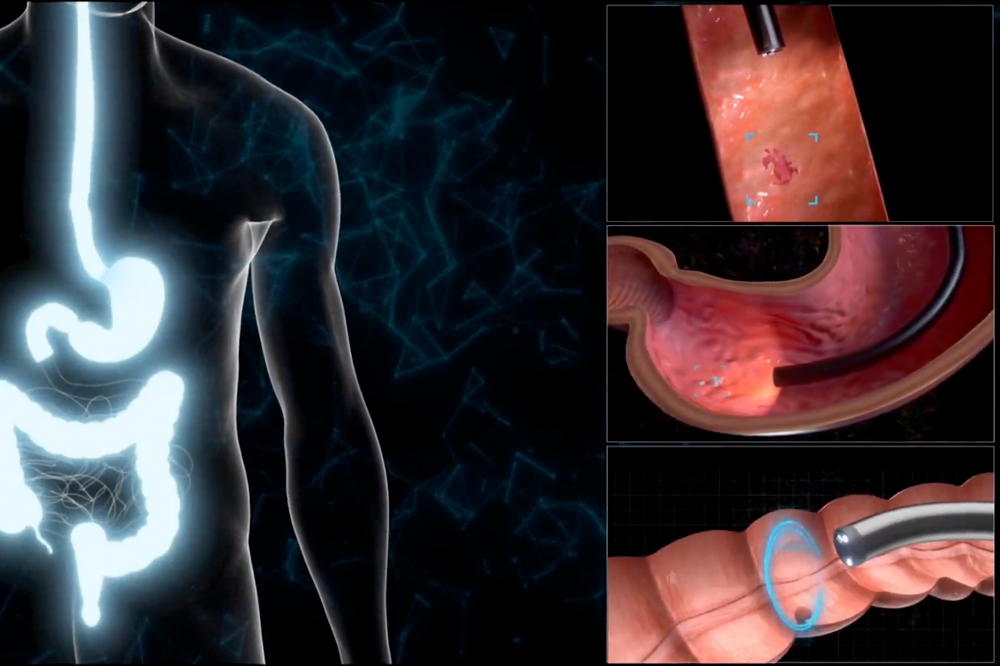

搭载双波长激光成像技术,通过特殊光谱精确照射观察部位,实时强化呈现黏膜表层血管网络与微细病变。结合AI辅助诊断系统,可在检查过程中即时标记可疑病灶,为医生提供精准的决策支持。